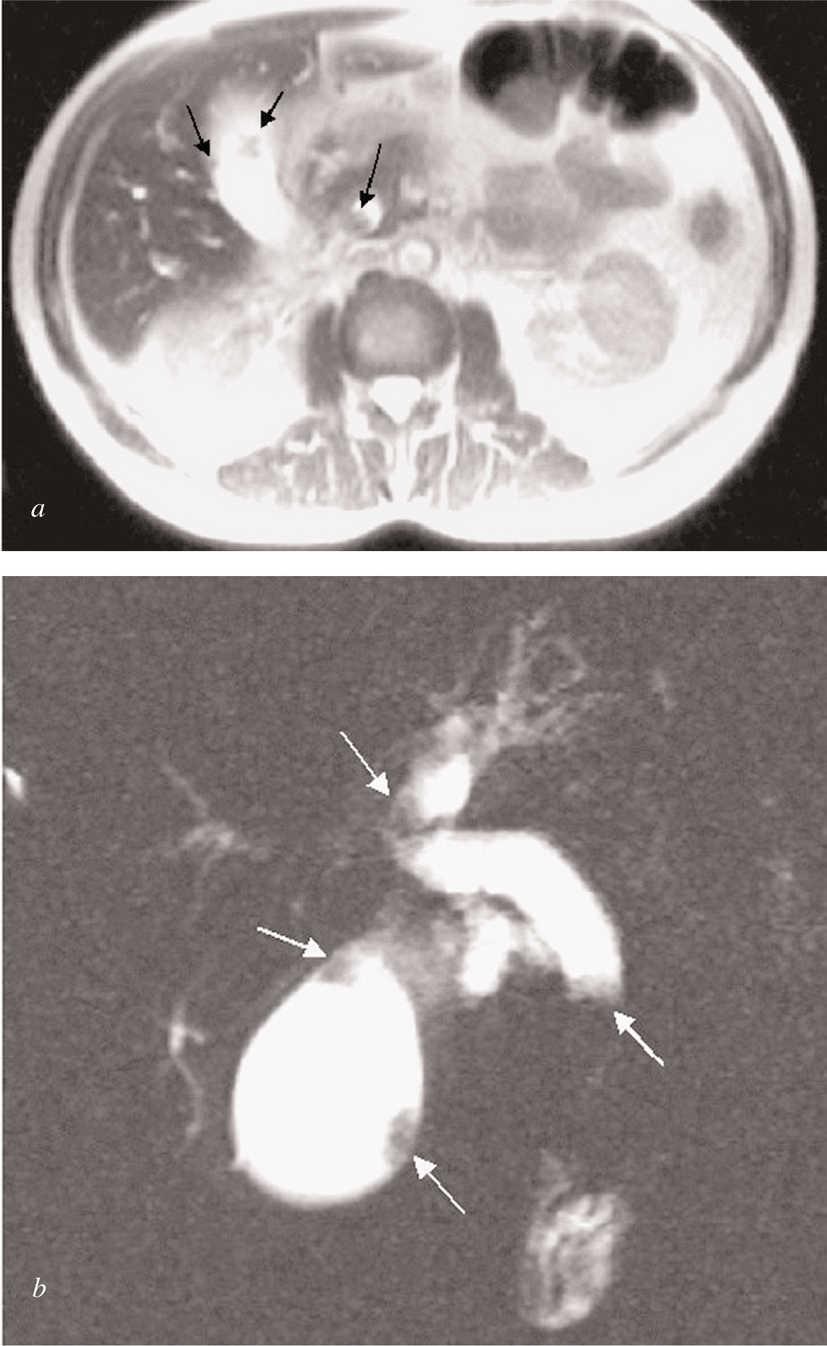

A 47-year-old man presented in July 2000 with progressive jaundice for 3-4 weeks, weakness, and anorexia leading to weight loss, as well as occasional right upper quadrant abdominal pain. He had been under treatment for a depressive syndrome for the previous 5 months and his medication had been changed due to a rise in serum aminotransferases. Liver function tests at admission showed pronounced cholestasis (total bilirubin 13.9 mg/dl, conjugated bilirubin 9.1 mg/dl, alkaline phosphatase 703 U/L, gamma glutamyl transferase 72 U/L) and mild hepatic cell necrosis (alanine aminotransferase 99 U/L (normal < 41 U/L) aspartate aminotransferase 44 U/L (normal < 37 U/L) without liver failure. Ultrasound showed intra- and extrahepatic bile duct dilation with several nodules on the gallbladder wall (fig. 1). Magnetic resonance cholangiopancreatography also revealed an obstructive tumor in the distal extrahepatic duct (figs. 2a-b). All lesions showed the same radiological pattern.

Fig. 1. Ultrasound revealed intra- and extrahepatic bile duct dilatation with multiple hyperechogenic polypoid mural masses in bile tree and gallbladder.